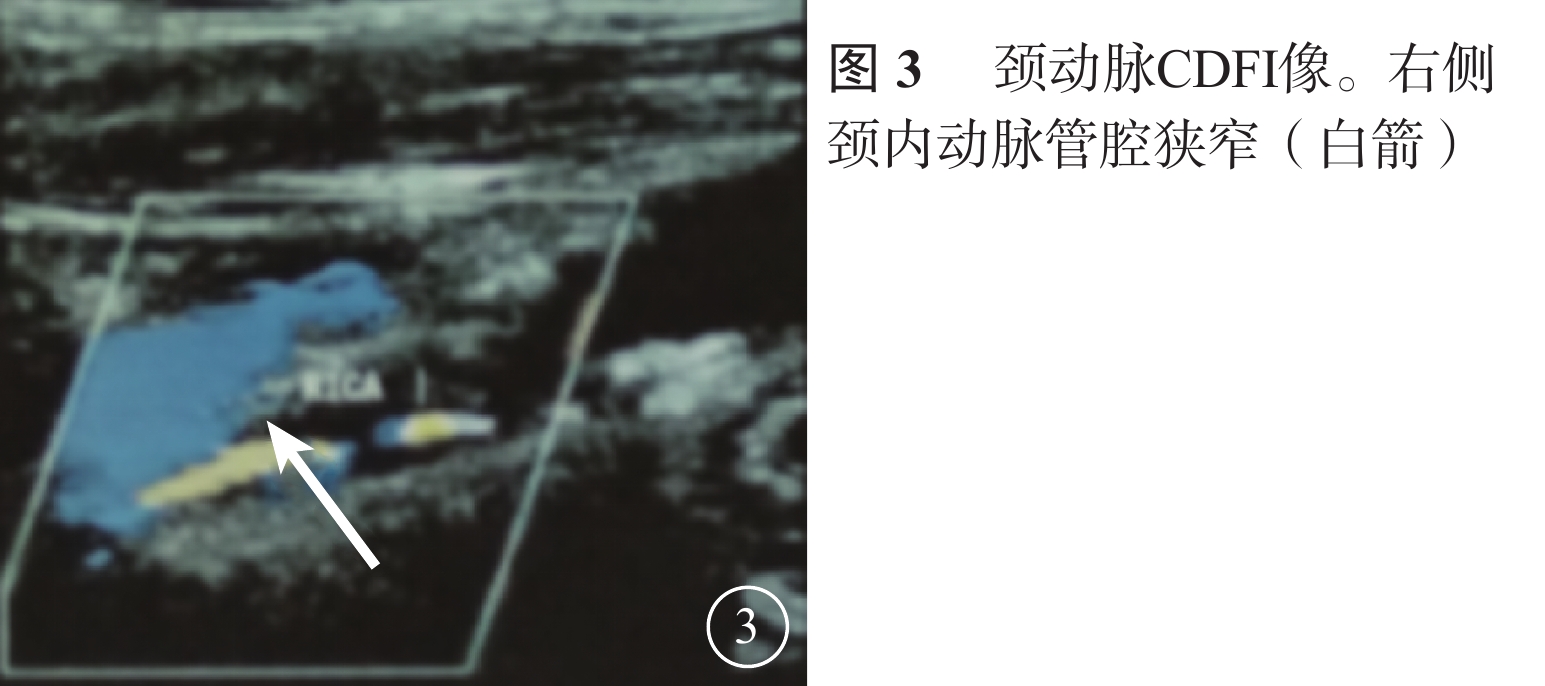

患者男,65歲。因右眼視物不見1周于2016年10月20日來我院就診。1周前無意中發現右眼視物不見,無眼紅、痛、畏光、流淚;自行使用芐達賴氨酸(商品名:莎普愛思)滴眼液滴眼無效而就診于外院。診斷為右眼新生血管性青光眼(NVG)?右眼視網膜病變(性質?);雙眼老年性白內障。既往高血壓病史8年,口服藥物治療。否認糖尿病、冠心病等其他全身病史。眼科檢查:右眼視力光感/眼前;左眼視力0.6,不能矯正。右眼眼壓17.3 mmHg(1 mmHg= 0.133 kPa),左眼眼壓12.7 mmHg。右眼前房深淺正常,周邊前房1 角膜厚度;瞳孔藥物性散大,邊緣全周可見虹膜新生血管(NVI),無后粘連;晶狀體混濁;玻璃體輕度混濁。眼底視盤邊界清楚,顏色橘紅,血管走形及比例基本正常;視網膜可見散在點片狀出血及片狀棉絨斑,黃斑中心凹反光不清(圖1)。左眼除晶狀體混濁、玻璃體輕度混濁,黃斑中心凹反光不清外,其余眼前節及眼底檢查未見明顯異常。熒光素眼底血管造影(FFA)檢查,右眼脈絡膜背景熒光充盈遲緩,視網膜動靜脈循環時間明顯延長(圖2)。光相干斷層掃描檢查,右眼后極部視網膜增厚,視網膜內層間反射信號大部分增強;左眼黃斑中心凹形態不規則。彩色超聲多普勒血流成像(CDFI)檢查,雙側頸總動脈、頸內動脈多發斑塊;右側頸內動脈管腔狹窄,約70%~99%(圖3)。頸動脈CT血管造影(CTA)檢查,顱內動脈硬化,可疑右側頸內動脈C1段重度狹窄;可疑兩側基底節區、右側丘腦腔隙性缺血灶。診斷:右眼眼缺血綜合征(OIS);雙眼老年性白內障;高血壓病。給予右眼玻璃體腔注射雷珠單抗0.05 ml治療。治療后3 d,視力數指/66 cm,眼壓15.0 mmHg;NVI完全消退。行右眼全視網膜激光光凝(PRP)治療。PRP治療后14 d檢查,右眼視力0.1;眼壓13.0 mmHg。轉血管外科行右側頸動脈內膜剝脫手術。手術后1個月復查,右眼視力0.4。FFA檢查,視網膜循環時間明顯改善(圖4)。

患者男,65歲。因右眼視物不見1周于2016年10月20日來我院就診。1周前無意中發現右眼視物不見,無眼紅、痛、畏光、流淚;自行使用芐達賴氨酸(商品名:莎普愛思)滴眼液滴眼無效而就診于外院。診斷為右眼新生血管性青光眼(NVG)?右眼視網膜病變(性質?);雙眼老年性白內障。既往高血壓病史8年,口服藥物治療。否認糖尿病、冠心病等其他全身病史。眼科檢查:右眼視力光感/眼前;左眼視力0.6,不能矯正。右眼眼壓17.3 mmHg(1 mmHg= 0.133 kPa),左眼眼壓12.7 mmHg。右眼前房深淺正常,周邊前房1 角膜厚度;瞳孔藥物性散大,邊緣全周可見虹膜新生血管(NVI),無后粘連;晶狀體混濁;玻璃體輕度混濁。眼底視盤邊界清楚,顏色橘紅,血管走形及比例基本正常;視網膜可見散在點片狀出血及片狀棉絨斑,黃斑中心凹反光不清(圖1)。左眼除晶狀體混濁、玻璃體輕度混濁,黃斑中心凹反光不清外,其余眼前節及眼底檢查未見明顯異常。熒光素眼底血管造影(FFA)檢查,右眼脈絡膜背景熒光充盈遲緩,視網膜動靜脈循環時間明顯延長(圖2)。光相干斷層掃描檢查,右眼后極部視網膜增厚,視網膜內層間反射信號大部分增強;左眼黃斑中心凹形態不規則。彩色超聲多普勒血流成像(CDFI)檢查,雙側頸總動脈、頸內動脈多發斑塊;右側頸內動脈管腔狹窄,約70%~99%(圖3)。頸動脈CT血管造影(CTA)檢查,顱內動脈硬化,可疑右側頸內動脈C1段重度狹窄;可疑兩側基底節區、右側丘腦腔隙性缺血灶。診斷:右眼眼缺血綜合征(OIS);雙眼老年性白內障;高血壓病。給予右眼玻璃體腔注射雷珠單抗0.05 ml治療。治療后3 d,視力數指/66 cm,眼壓15.0 mmHg;NVI完全消退。行右眼全視網膜激光光凝(PRP)治療。PRP治療后14 d檢查,右眼視力0.1;眼壓13.0 mmHg。轉血管外科行右側頸動脈內膜剝脫手術。手術后1個月復查,右眼視力0.4。FFA檢查,視網膜循環時間明顯改善(圖4)。